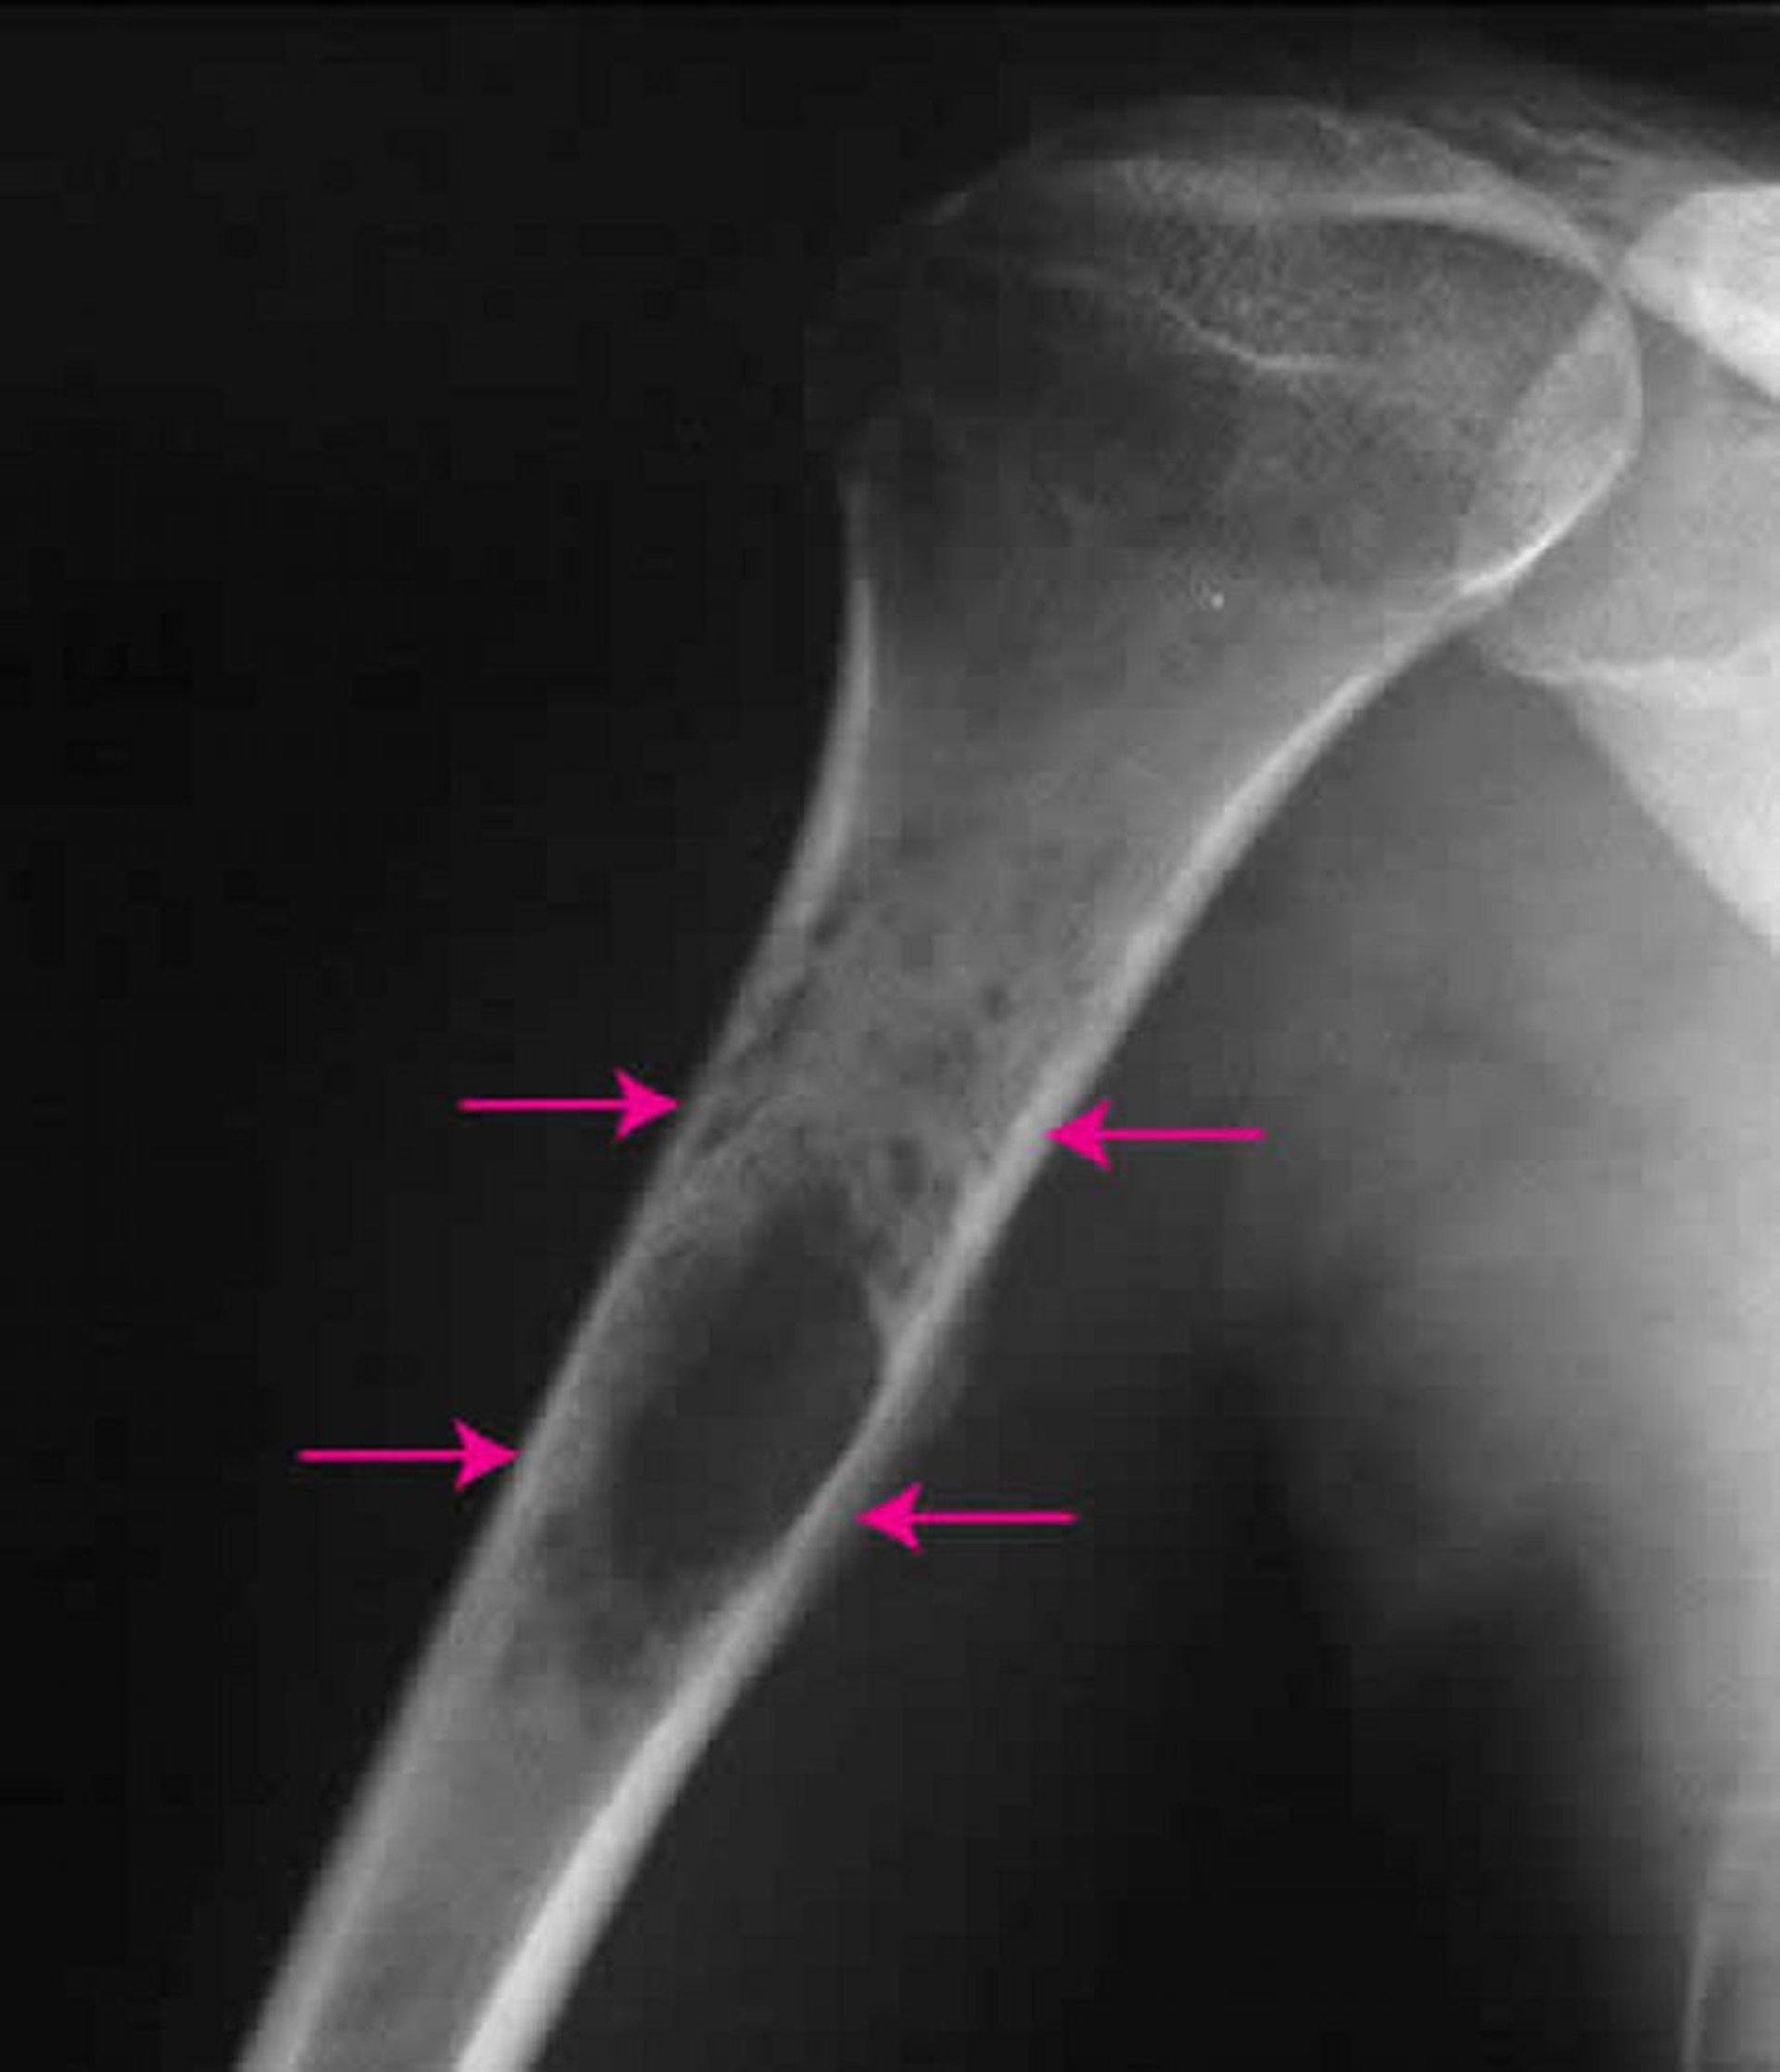

ساركومة يُوينغ العظمية

تُظهر هذه الصورة الشعاعية للكتف كيسة يوينغ العظمية (اتجاه الأسهم) في عظم العضد.

جرى استخدام الصورة بعد موافقة أصحابها Michael J.Joyce, MD, and Hakan Ilaslan, MD.